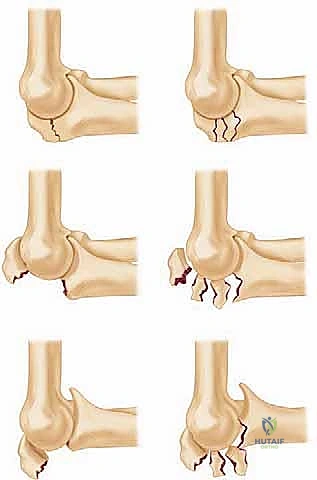

Fracture characteristics – displacement, comminution, and any associated subluxation or dislocation of the elbow – are crucial. We categorize these using systems like the Mayo classification, which helps guide our treatment decisions.

Image

FIG 1 • The Mayo classification of olecranon fractures accounts for the factors that will influence treatment decisions: displacement, comminution, and dislocation or subluxation of the articulations.